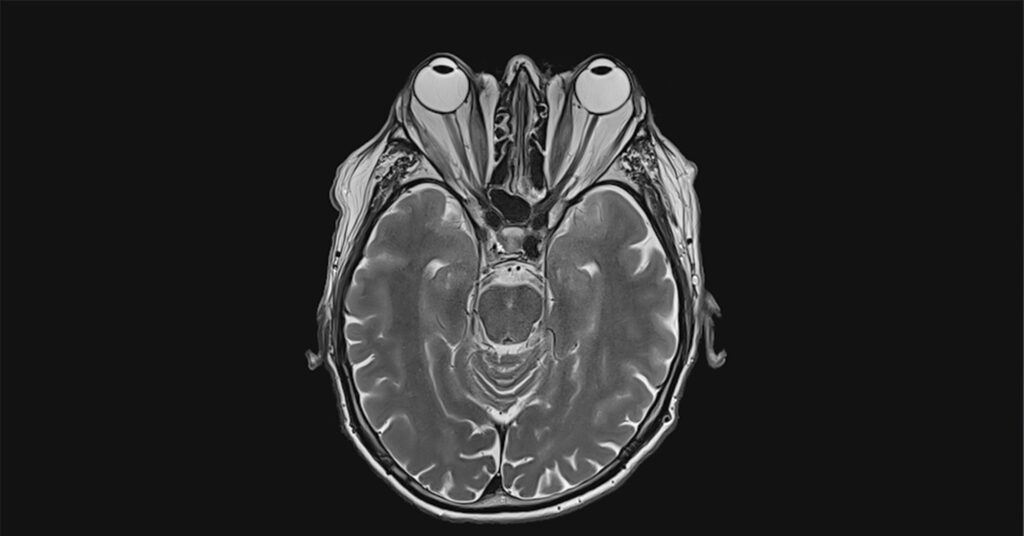

Depuis une année, cet homme de 39 ans ne sait plus à quel saint se vouer pour trouver une solution permanente à sa maladie. En effet, plus d’une année s’est écoulée qu’il souffre de l’exophtalmie, une forme de gonflement de son œil, causé par un problème d’hyperthyroïdie. À tel point que Louis Charlondon Antoine ne peut pas fermer son œil, même quand il dort.